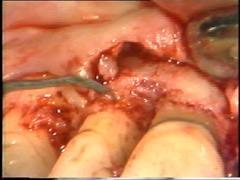

En la superficie

palatina del central, hay un defecto grande en la superficie de la raíz. Probablemente

sea una fractura que ocurrió en relación con el accidente. El tejido de

granulación se ha formado en el defecto que se limpia completamente. Postoperatoriamente es necesario poner

apicalmente el colgajo en relación con el defecto de la raíz para crear una condición higiénica manejable

|